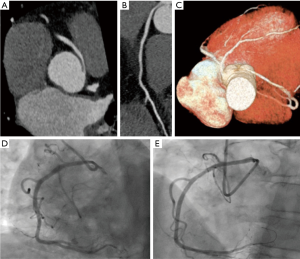

The case is presented in a multidisciplinary session, where because the absence of inducibility of ischemia in the performed tests, it is decided to manage conservatively. Subsequently, the patient is followed in our outpatient clinic remaining asymptomatic. In addition, stress echocardiography is performed during the follow-up, with the intention of actively discard subclinical ischemia in the evolution, which is negative (Figure 1).

The case of patient number 2 is completely different. In this case, despite the history of negative ischemia induction tests, it presents an evident compression in the interarterial pathway (Figure 3). This is evidenced by both the Coronary Angio CT and the Coronary Artery Angiography. This is important because despite initially negative ischemia tests, any kind of compression or obstruction that compromises the vascular caliber should always be carefully discarded. Accordingly to clinical practice guidelines, these patients are also candidates for revascularization for symptomatic improvement and risk of SD reduction, despite the presence of negative ischemia detection tests.